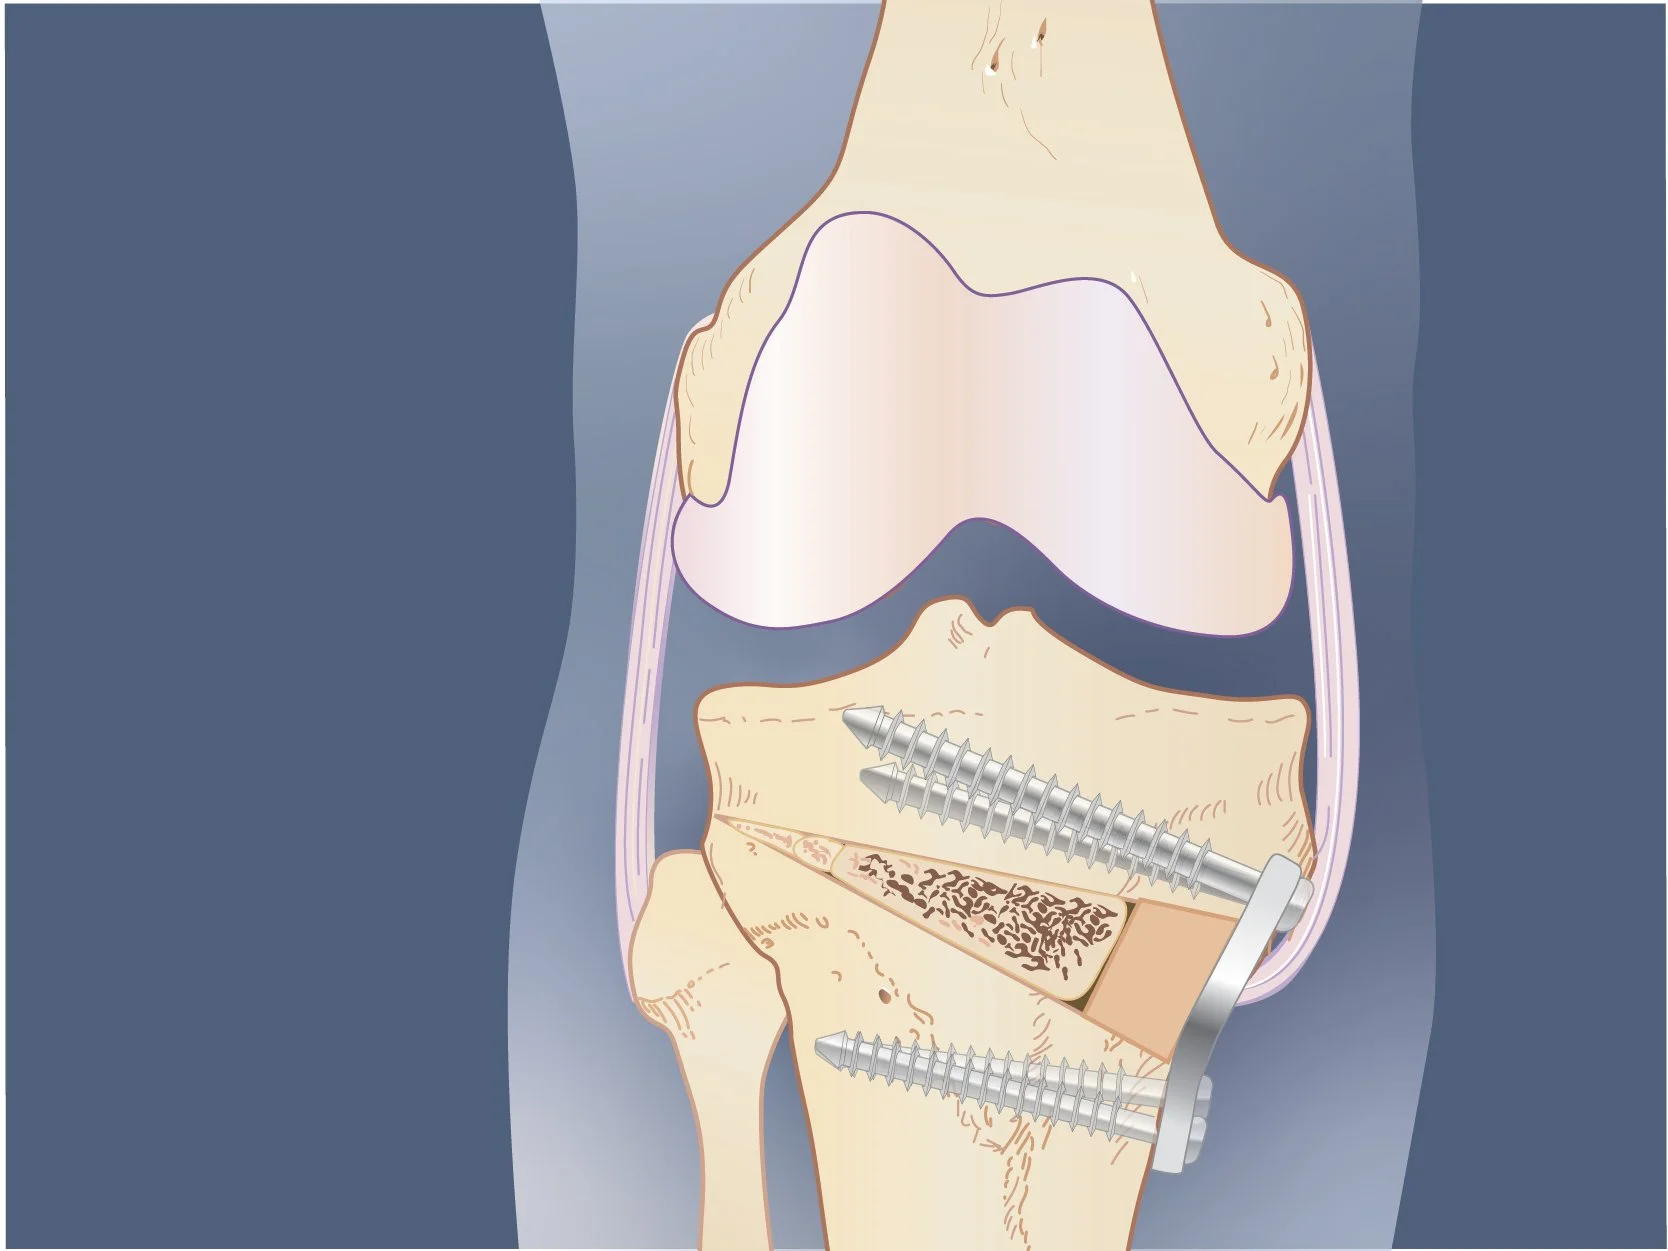

Surgical illustrations visually depict operative techniques, surgical anatomy, and complex procedures. They are created with high anatomical accuracy and serve as a visual bridge between complex surgical knowledge and learners, clinicians, or patients.